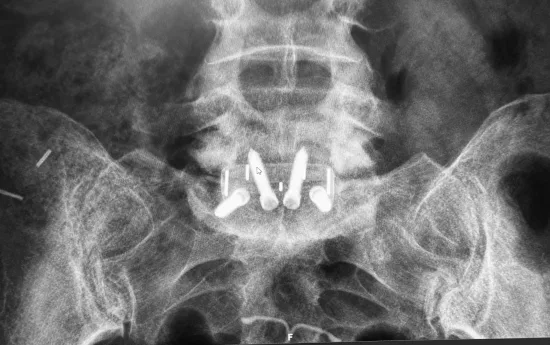

Compresión grave de la médula espinal o de las raíces nerviosas, evidenciada en estudios de imagen como resonancia magnética o tomografía computarizada.

Fusión espinal: En algunos casos, especialmente cuando hay inestabilidad espinal, puede ser necesaria una fusión vertebral para estabilizar la columna vertebral después de la cirugía de descompresión. Esto implica fusionar dos o más vértebras.